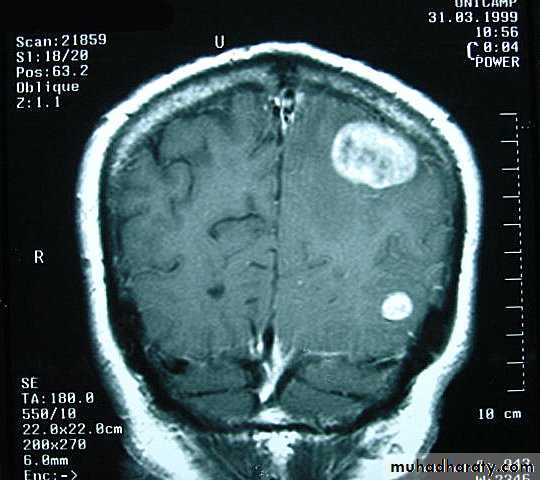

Metastatic Brain TumoursMRI